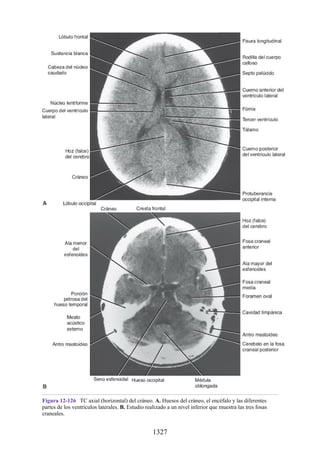

que unen la cintura escapular con el tronco se contraen como estabilizadores

para permitir la acción del músculo deltoides en el hombro (véase fig. 1-17C).